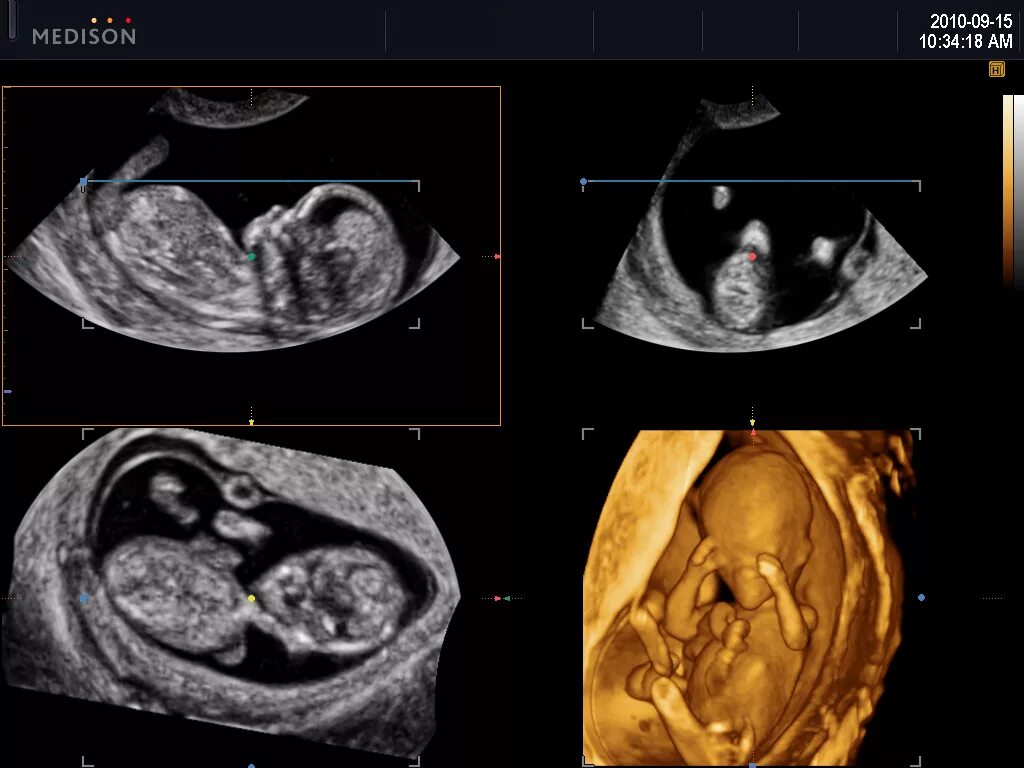

На каком сроке делать 3д